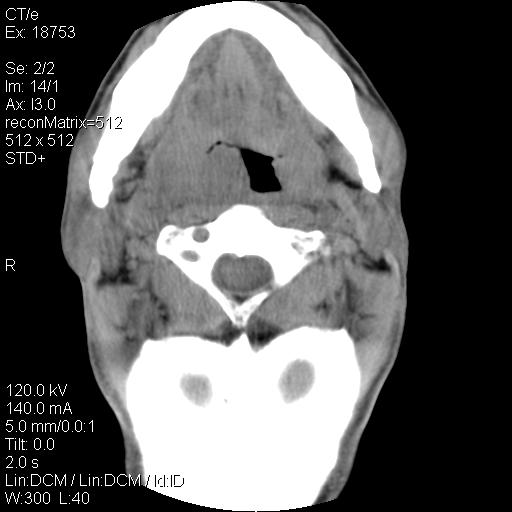

标题: CT21693:男 58岁 右侧咽部疼她2天余 PE:右侧扁桃体肿大 压痛 [打印本页]

标题: CT21693:男 58岁 右侧咽部疼她2天余 PE:右侧扁桃体肿大 压痛

弥漫性肿胀,与周围组织分界不清,发病急,有明显症状,考虑:感染性病变!

弥漫性肿胀,与周围组织分界不清,发病急,有明显症状,考虑:感染性病变! 抗炎后复查。

右化脓性扁桃体炎症伴咽后壁脓肿形成.